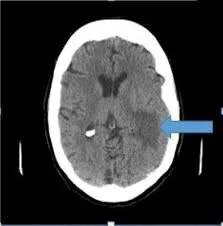

Collections of blood that form in the subdural space in the brain are common in patients 50 years and older, with head trauma the common cause. The subdural space is the area between the brain surface and the dura (covering) of the brain.